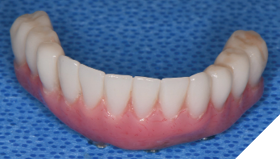

The patient returned 2 weeks from the impressioning appointment for a prototype try in. At this appointment the esthetics, phonetics, soft tissue approximation and occlusion were confirmed. There was no requirement for a verification jig due to the accuracy of the Nexus solution. The restorations were manufactured with milled gold anodized titanium bars overlaid with monolithic zirconia (Figs. 24A-C, 25A-C).

The patient returned 2 months later (due to patient scheduling delays) and the maxillary and mandibular Nexus restorations were inserted (Figs. 26A-C). Passive seating of the restorations were confirmed with the Sheffield test and radiographic confirmation. The occlusion was checked and final radiographs taken (Fig. 27).